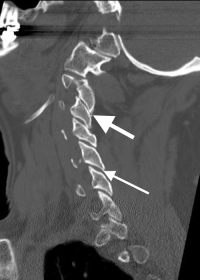

The last function of the bilateral facets is that of a doorstop. The upper facets are angled backwards and “hook into” the lower facets of the vertebra below. This link prevents the upper vertebra from sliding forward on the lower vertebra (I like to call this the doorstop mechanism). When the facets wear out, this link is broken and the upper vertebra can abnormally slide forward on the lower vertebra (degenerative spondylolisthesis or anterolisthesis). This shifting can be painless or produce instability pain along with possible nerve and spinal cord impingement.

(Click to Enlarge Image) Lateral X-Ray of the neck with a forward bend (flexion). Note the vertebra slipping forward. The black arrows point to the forward slide and forward angulation of the vertebra.